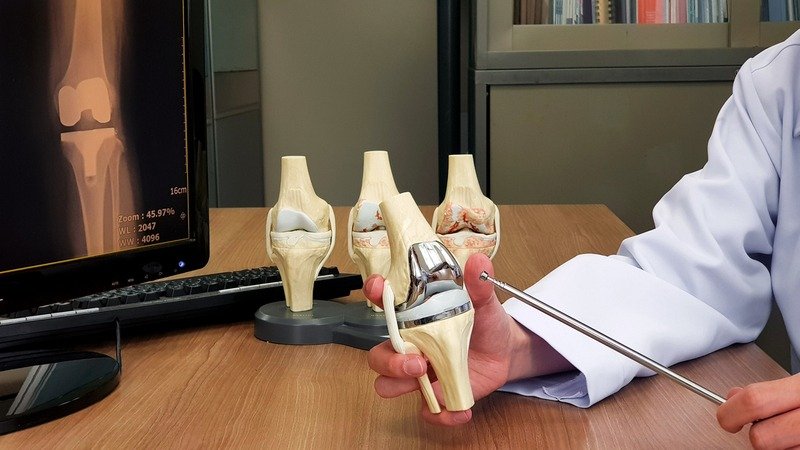

India has several internationally recognized transplant centers offering:

- Dedicated organ transplant units

- Advanced ICUs with critical care monitoring

- Experienced transplant surgeons and teams

- Modern diagnostic and surgical technology

- International patient coordination departments

These hospitals ensure safe, precise, and high-quality surgical outcomes for international patients.